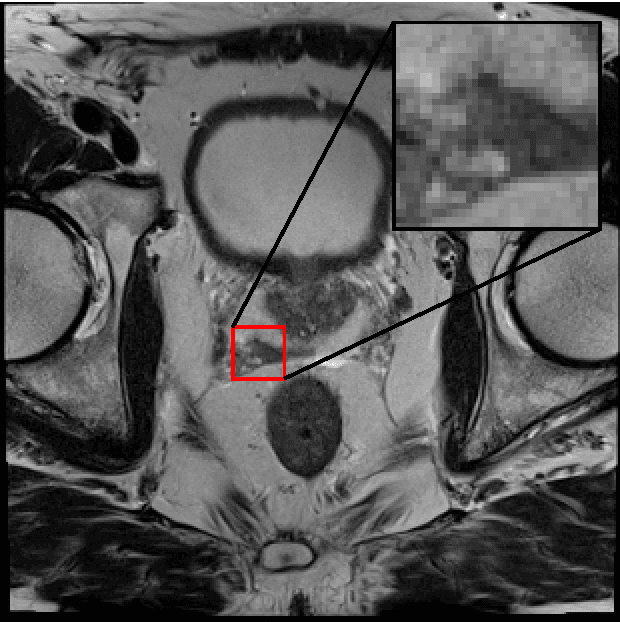

Generative Adversarial Neural Networks (GANs) are applied to the synthetic generation of prostate lesion MRI images. GANs have been applied to a variety of natural images, is shown show that the same techniques can be used in the medical domain to create realistic looking synthetic lesion images. 16mm x 16mm patches are extracted from 330 MRI scans from the SPIE ProstateX Challenge 2016 and used to train a Deep Convolutional Generative Adversarial Neural Network (DCGAN) utilizing cutting edge techniques. Synthetic outputs are compared to real images and the implicit latent representations induced by the GAN are explored. Training techniques and successful neural network architectures are explained in detail.